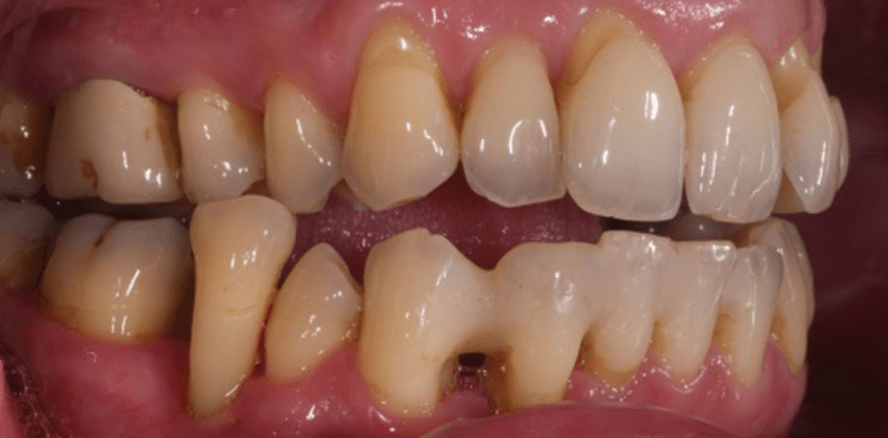

Die zum Zeitpunkt der Erstvorstellung 49-jährige Patientin bemerkte die Lockerung und Verlängerung des Zahnes 45 schon mehrere Monate, dies führte auch zu einer Bisssperrung, die von der Patientin toleriert wurde (Abb. 1–3). Der Zahn war vital, Sondierungstiefen 5–11 mm, LG III. Die Mundhygiene war befriedigend. Nach Besprechung der Behandlungsalternativen (Extraktion und Lückenschluss durch Brücke oder Implantation) wurde über die Möglichkeit der Transreplantation aufgeklärt.